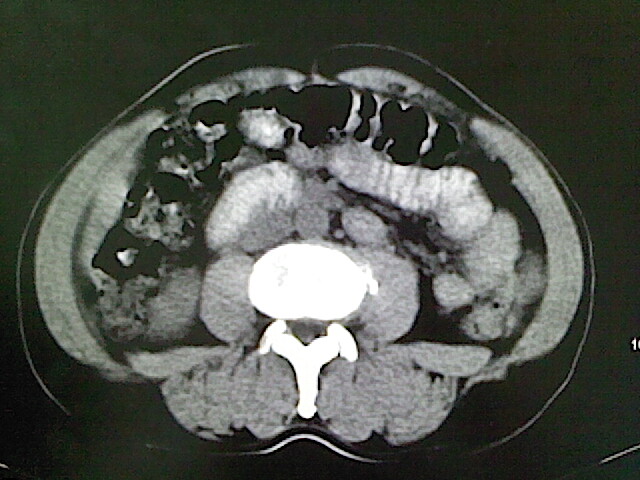

标题: CT18630:男,54岁,乙肝,大家看怎么样? [打印本页]

男,54岁,乙肝,大家看怎么样?

医学影像诊断的基本原则之一是密切结合临床,请你提供简明扼要的病史。

未见明确异常;建议必要时行ct增强扫描检查。